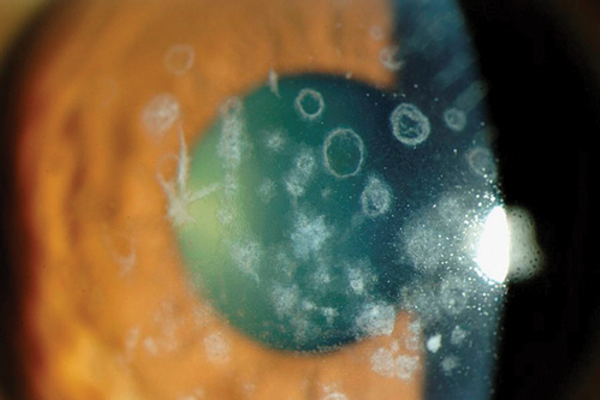

Corneal dystrophies simplified

Sejal Bhatt

·

1st December 2016

Education